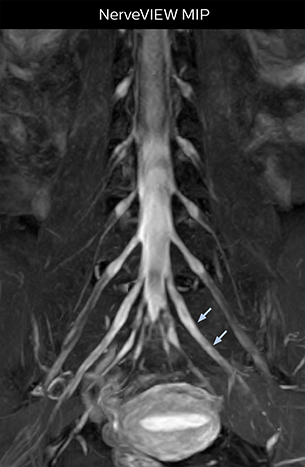

Distinguishing typical from atypical herniation informs the surgeon

“NerveVIEW is really useful for those cases where a nerve disorder is strongly suspected based on the clinical examination but our regular MRI images do not show any findings. These atypical herniations and spinal canal stenosis, occurring in 5% to 15% of the total lumbar herniation/stenosis cases are our main target when using NerveVIEW,” says Dr. Yabuki.

“Although symptoms of typical disc herniation and atypical hernia are very similar, the actual site of herniation is different. It is therefore important to characterize the nerve’s condition both inside and outside of the intervertebral foramina.

“Conversely, if we see no abnormality in NerveVIEW, we can assume at least that there is no severe condition that requires surgery. Like this, it can help us avoid unnecessary surgery. NerveVIEW can have a tremendous impact in this way.”